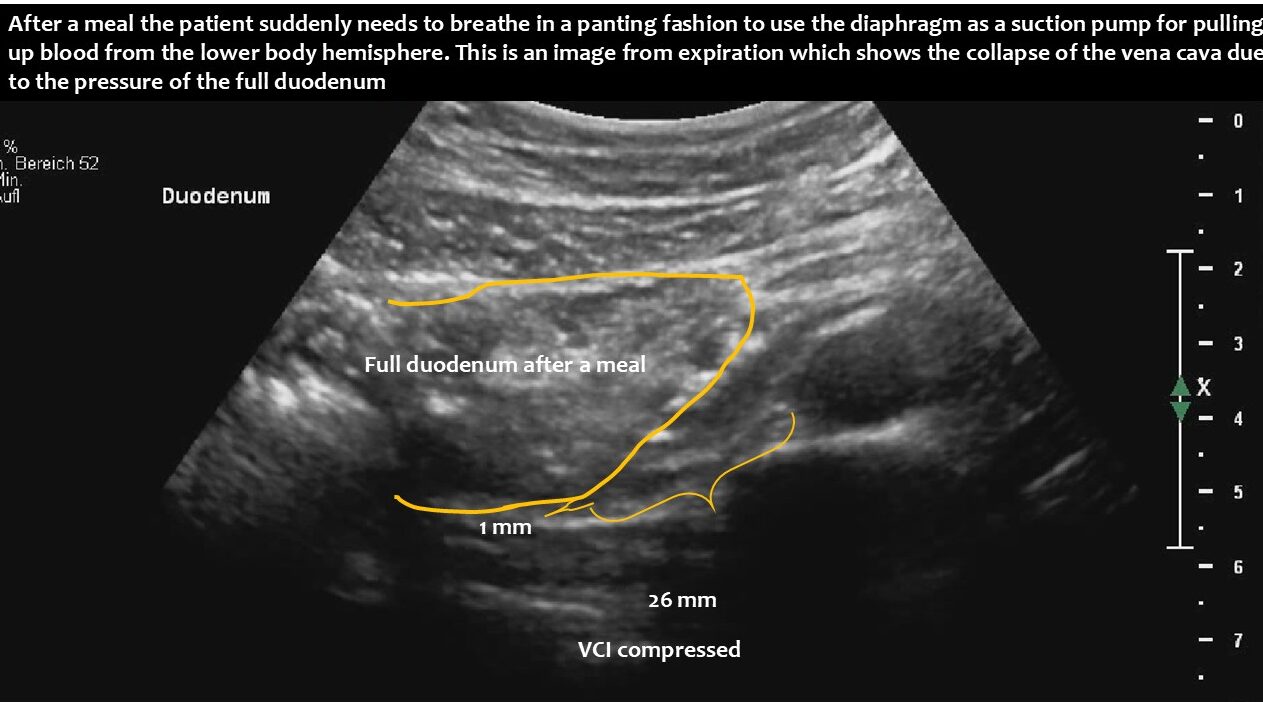

Immediately after food was taken up, the stomach pumped it into the duodenum, which subsequently enlarged and compressed the vena cava.

This suddenly interrupted or massively compromised the venous return from the lower body hemisphere. This led to a sudden drop in the circulating blood volume. Due to reduced lung perfusion as a consequence of the reduction in central flow volume, panting developed to enhance oxygenation of the remaining small blood volume. At the same time, the reduced blood flow to the brain, in combination with hypocapnia as a result of hyperventilation to fight imminent compromise of oxygenation, caused dizziness and a sensation of near fainting.

Functional ultrasound can demonstrate the entire pathophysiological chain, from underlying lordosis to postprandial duodenal enlargement and subsequent vena cava compression, especially when standing after eating.